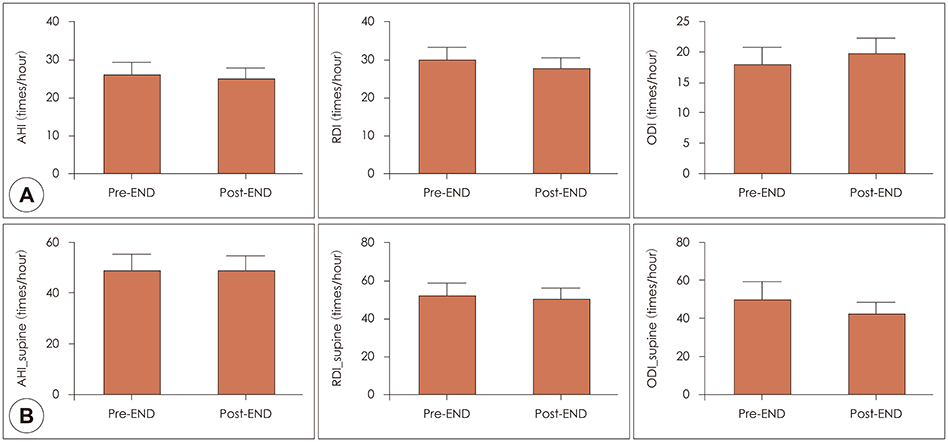

In 13 patients with OSA, changes of total nasal volume (TNV) and minimal cross-sectional area (MCA) before and after END use were evaluated. The change in peak nasal inspiratory flow (PNIF) was also measured. Subjects completed Epworth Sleepiness Scale questionnaire before and 2 weeks after END use. Finally, changes in apnea-hypopnea index (AHI), respiratory distress index (RDI), oxygen desaturation index (ODI), sleep time, sleep position and loudness of snoring (in decibels) were obtained by repetitive portable polysomnography.

RESULTS

After END use, TNV (11.4±3.1 cm3 to 19.4±5.7 cm3) and MCA (0.7±0.2 cm2 to 0.9±0.1 cm2) increased significantly (p=0.001). PNIF also increased significantly after END (147.3±39.5 to 194.6±57.6 liter/min, p=0.001). Among 11 patients undergoing 2-week follow-up, 7 reported improvement in daytime sleepiness. Although AHI, RDI and ODI showed no statistically significant change before and after END (p>0.05), the proportion of subjects sleeping in the supine position increased from 38.0 to 44.5%.